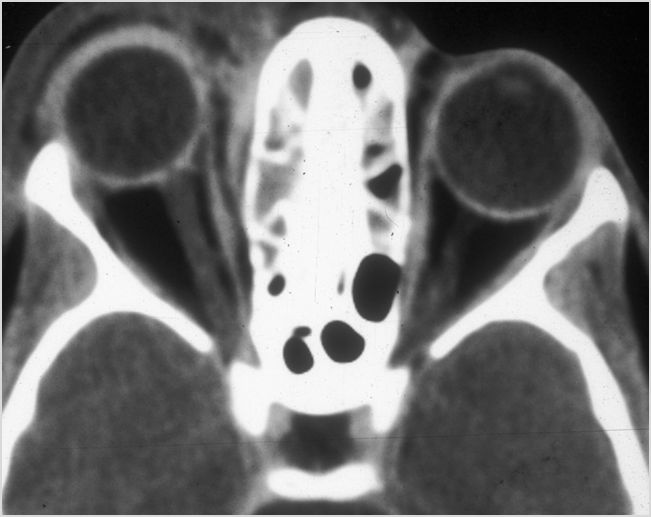

The extraconal orbital fat is abnormal. [Yes/No]

There is a subperiosteal abscess or edema along the medial wall, roof or floor of the orbit. [Yes/No]

The extraocular muscles are swollen or otherwise abnormal. [Yes/No]

The intraconal orbital fat is infiltrated. [Yes/No]

The orbital apex and the superior and inferior orbital fissures are infiltrated. [Yes/No]

The superior and/or inferior ophthalmic veins are dilated or thrombosed. [Yes/No]

Proptosis is present. [Yes/No]

The optic nerve is stretched in appearance. [Yes/No]

The posterior aspect of the globe is tented in appearance. [Yes/No]